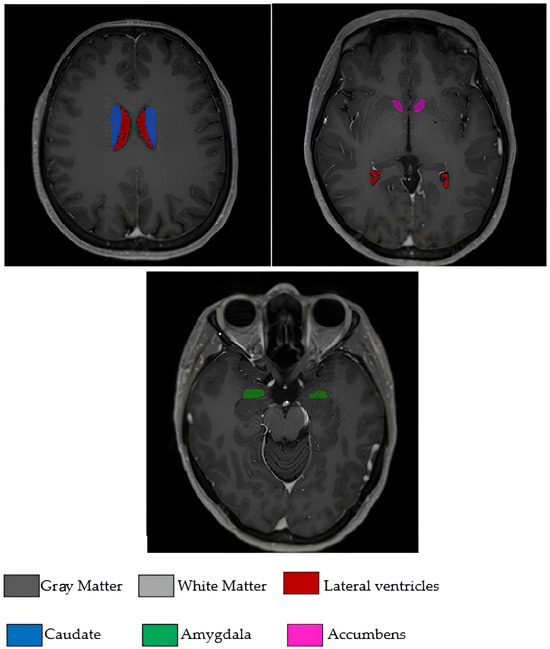

The 17 brain morphological features used in the study were as follows: age, white matter volume (WM), gray matter volume (GM), cerebrospinal fluid volume (CSF), total brain volume (Brain WM + GM), intracranial cavity volume (IC), cerebrum volume, cerebellum volume, brainstem volume, lateral ventricle volume, caudate nucleus volume, putamen volume, thalamus volume, globus pallidus volume, hippocampus volume, amygdala volume, and nucleus accumbens volume. All volumetric measurements were expressed in cubic millimeters (mm3). These volumetric measurements encompass critical brain regions that reflect the neurodegenerative processes of PD and were obtained from clinical radiology reports following standardized measurement protocols. The analysis focused exclusively on quantitative volumetric features extracted from clinical assessments, with no image processing performed in this study. To visually illustrate the input features used for model training and interpretation, Figure 1 displays selected brain regions extracted from the original T1-weighted MRI scans included in the study dataset. Although a total of 17 volumetric features were analyzed, Figure 1 highlights several anatomically and clinically relevant regions that were emphasized by the model during classification.

Figure 1. Axial T1-weighted MRI slices illustrating some of the brain regions used in the model.